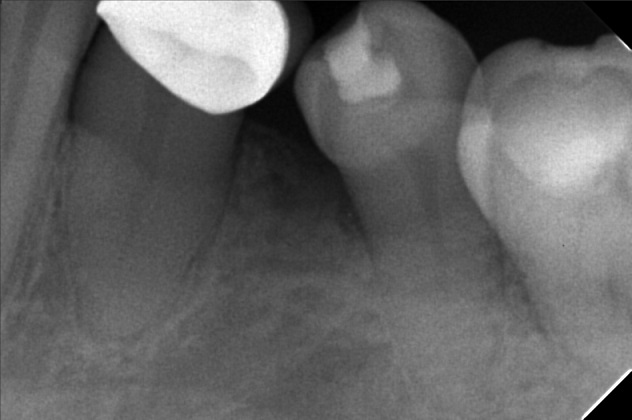

- 6/1/22- perio Tx / deep scaling laser curettage/ laser hypersensitivity/ next meeting FIRST WK august ***for change crown 9/10/22- stain removal 9/17/22 - check up for change crown

- rosario.jpg